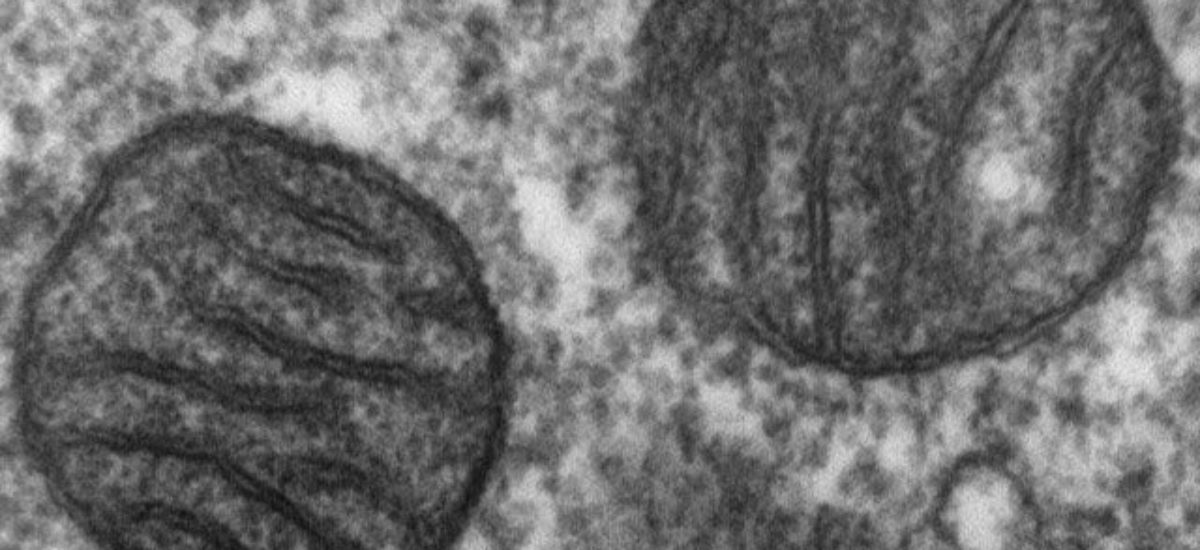

Las mitocondriopatías son muchas y muy diferentes enfermedades con un origen común. Todas ellas están causadas por la alteración de una parte de las células, las mitocondrias. Estos orgánulos, u organelos, están en su interior -de la misma forma que los órganos en el cuerpo humano- y tienen un papel muy importante en los organismos vivos. Las mitocondrias son la “fábrica” de energía de las células y las encargadas de su respiración.

Debido a la importancia de las funciones que ejercen, están implicadas en múltiples enfermedades y procesos biológicos, como el envejecimiento. Por ello, es básico conocer cómo funcionan y qué implicaciones tienen en diversas patologías. Ni las mitocondrias ni el daño mitocondrial deberían ser ajenos al conocimiento de la población general, ya que la afectación de éstas se ha relacionado con enfermedades tan conocidas como el Alzheimer y el Parkinson, u otras minoritarias como la Corea de Huntinton.

Los tipos de mitocondriopatías son muchos y muy heterogéneos. La bióloga e investigadora Constanza Morén, del Instituto de Investigaciones Biomédicas August Pi i Sunyer (IDIBAPS), en Barcelona, asegura que la explicación científica es la siguiente: las mitocondrias son capaces de reproducirse en el interior de la célula de forma independiente, con su propio genoma, el ADN mitocondrial (ADNmt). Su gran capacidad para mutar se relaciona con la complejidad de las alteraciones en las enfermedades causadas por mitocondrias.

Cada célula del cuerpo tiene cientos de moléculas de ADNmt. Al dividirse la célula para formar células hijas, este ADN alterado se distribuye al azar. El resultado es la aparición de numerosas y muy distintas enfermedades, que pueden estar causadas por anomalías en las mitocondrias. Aunque cada tejido destaca por diferentes capacidades para eliminar los orgánulos defectuosos, algunos quedan dañados por distintas razones, como el estrés oxidativo y la acumulación de calcio.